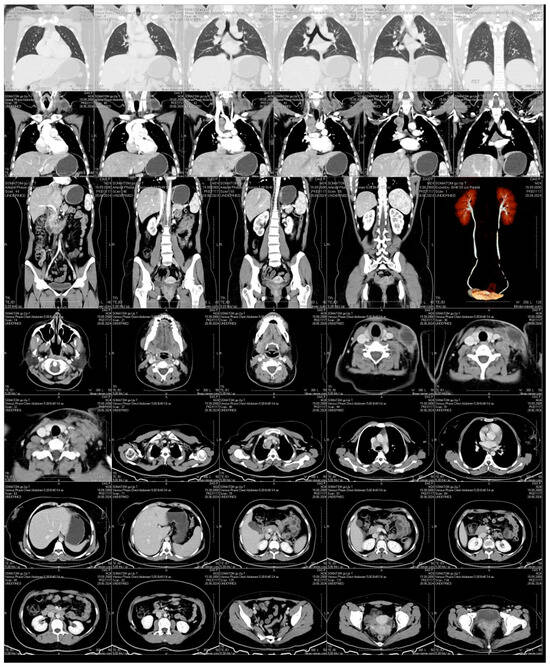

Neck ultrasound demonstrated bilateral hypoechoic lymphadenopathy with increased vascularity. CT imaging revealed a large, encapsulated fluid collection in the left supraclavicular area, alongside enlarged paratracheal and subcarinal lymph nodes with necrotic changes (Figure 3). No pulmonary lesions or abdominal pathology were noted. Imaging was performed using a Philips iU22 ultrasound system with a high-frequency linear probe (12–15 MHz) for detailed soft tissue imaging. CT scanning was carried out on a Siemens Somatom Definition AS 64-slice CT scanner (Siemens Healthineers, Forchheim, Germany), with contrast enhancement for better visualization of the fluid collection and lymph node enlargement.

Figure 3.

Contrast-Enhanced CT Scan. An encapsulated fluid collection with well-defined margins is visualized in the left supraclavicular region, consistent with an abscess or a necrotically transformed lymph node. Prominent lymphadenopathy is also observed in the paratracheal and subcarinal regions, with evidence of central necrosis. No signs of pulmonary involvement or abdominal pathology are detected.